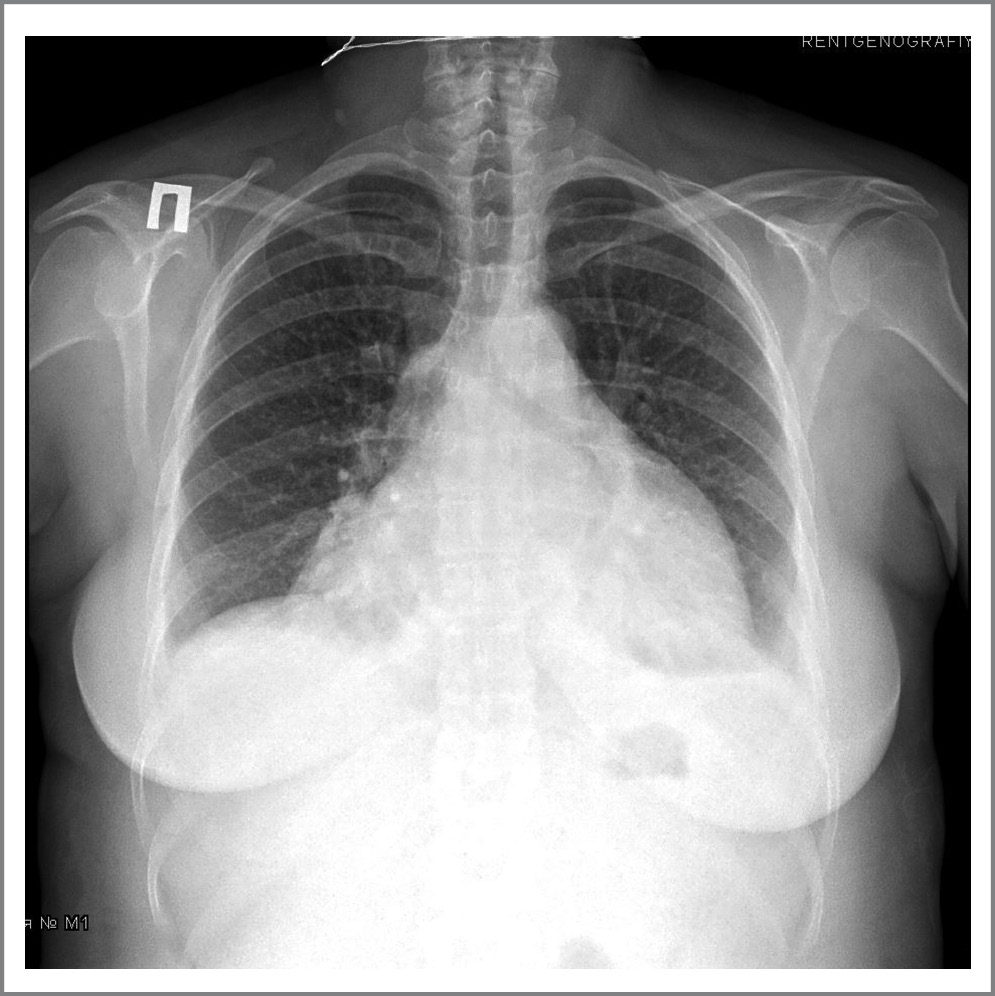

Эхокардиография. Камеры сердца не расширены. Размеры обоих предсердий на верхней границе нормы. Митральная и трикуспидальная регургитация до 1-й степени. Глобальная и локальная сократимость левого желудочка не нарушена. Диастолическая дисфункция левого желудочка. Признаки умеренной легочной гипертензии. Большое количество жидкости в полости перикарда с признаками сдавления сердца (тампонада); рис. 2.

Рис. 2. Эхокардиограмма больной К.

Fig. 2. Echocardiogram of patient K.